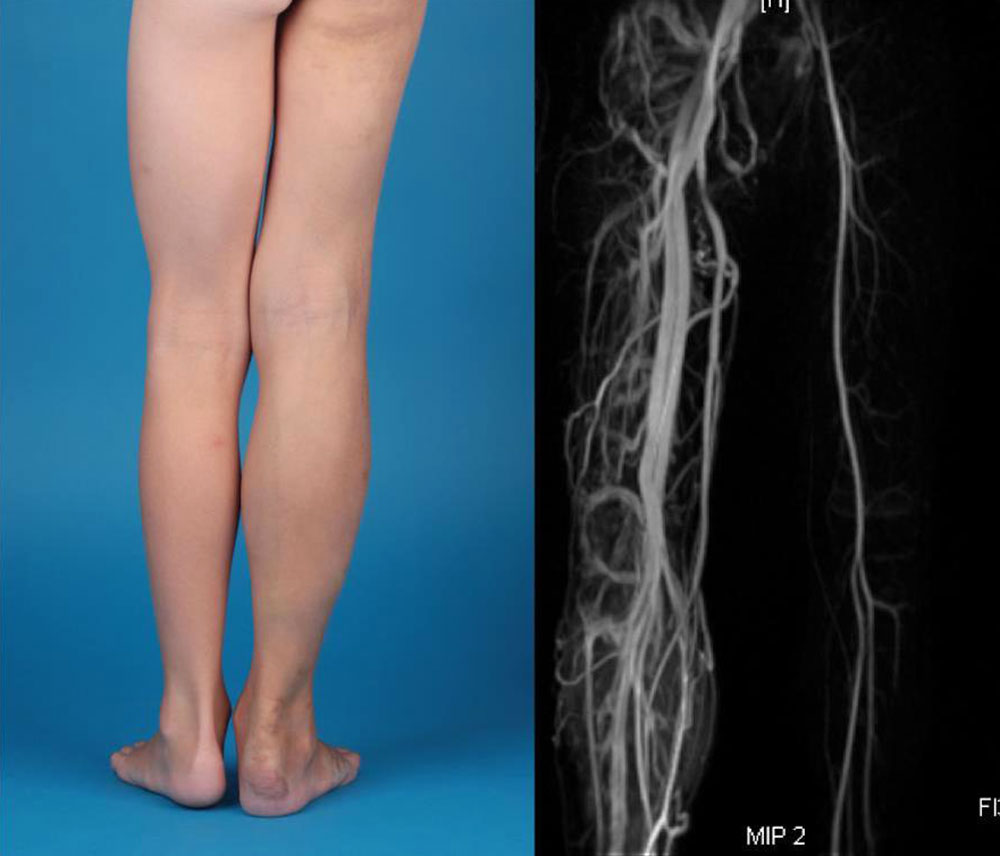

Vascular malformations (simple and combined) “associated with other anomalies” may be combined with non-vascular, mainly osseous, muscular, or fatty tissue growth anomalies. They often involve circumscribed overgrowth affecting a body region or whole body quadrant, e.g., a vascular malformation combined with overgrowth of a whole leg including buttocks or an arm including the shoulder. The manifestation will, therefore, always be a combination of malformation of vessels and soft tissue or bone. However, other visceral, cerebral or cardiac anomalies may also be associated in the sense of complex syndromes. These are mainly overgrowth syndromes and much less frequently undergrowth syndromes; however, overgrowth and undergrowth may be present at the same time in the same patient. Based on the ISSVA classification, the following table provides an overview of the classification of vascular malformations associated with other anomalies. The syndrome names listed here are often avoided nowadays, as they are not precisely defined in many cases. It is now preferable to use the symptom manifestation in the individual case, which can vary from patient to patient, in order to define the diagnosis according to the underlying vascular or other anomaly. Thus, a patient’s condition may not be referred to as Klippel-Trénaunay syndrome, but the more precise and meaningful term “combined capillary venolymphatic malformation with limb overgrowth” may be chosen.

| CM + AVF + overgrowth of extremities | Parkes Weber syndrome |